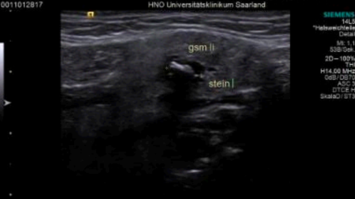

Neben der Beurteilung von Tumoren können mittels Ultraschall auch verschiedenste Pathologien der Kopfspeicheldrüsen untersucht werden. Die Kopfspeicheldrüsen produzieren in der Regel den für den Menschen wichtigen Speichel. Aufgrund verschiedenster Erkrankungen, wie beispielsweise Speichelsteine oder Tumore, aber auch durch chronische Veränderungen des Drüsengewebes, kann die Speichelproduktion eingeschränkt werden. Des Weiteren ist der Ultraschall in der Planung von operativen Eingriffen ein unabdingbares Hilfsmittel. Der Operationsumfang kann bereits präoperativ sehr gut eingeschätzt und die Patientinnen und Patienten über die operativen Risiken bestmöglich aufgeklärt werden. Bei Vorliegen von Speichelsteinen kann durch eine Ultraschalluntersuchung eingeschätzt werden, inwieweit eine Entfernung des Steins über den Mund, endoskopisch oder über eine Schlitzung des Ausführungsganges, erfolgen kann oder ob mit einer kompletten Drüsenentfernung gerechnet werden muss.